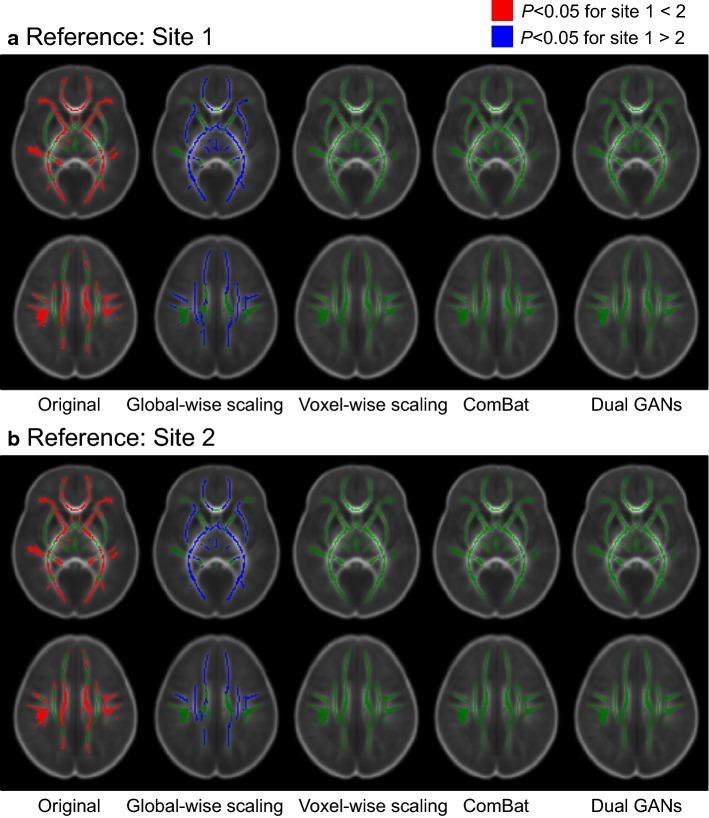

DTI-derived metrics (fractional anisotropy, FA; mean diffusivity, MD) are obtained on age-matched neonates without magnetic resonance imaging (MRI) abnormalities: 42 neonates from site 1 and 42 neonates from site 2. Significant inter-site differences of FA can be observed. The proposed harmonization approach and three conventional methods (the global-wise scaling, the voxel-wise scaling, and the ComBat) are performed on DTI-derived metrics from two sites. During the tract-based spatial statistics, inter-site differences can be removed by the proposed dual GANs method, the voxel-wise scaling, and the ComBat. Among these methods, the proposed method holds the lowest median values in absolute errors and root mean square errors. During the pooling analysis of two sites, Pearson correlation coefficients between FA and the postmenstrual age after harmonization are larger than those before harmonization. The effect sizes (Cohen's d between males and females) are also maintained by the harmonization procedure.

对无磁共振成像(MRI)异常的年龄匹配新生儿进行了 DTI 衍生指标(各向异性分数,FA;平均弥散度,MD)的测量:站点 1 有 42 例新生儿,站点 2 有 42 例新生儿。可以观察到 FA 存在显著的跨站点差异。在来自两个站点的 DTI 衍生指标上,应用了所提出的协调方法和三种传统方法(全局比例缩放、体素比例缩放和 ComBat)。在基于束的空间统计学中,通过所提出的双 GANs 方法、体素比例缩放和 ComBat 可以消除跨站点差异。在这些方法中,所提出的方法在绝对误差和均方根误差的中位数值最低。在两个站点的汇总分析中,协调后 FA 与孕龄后的 Pearson 相关系数大于协调前的相关系数。协调过程还保持了效应大小(男性和女性之间的 Cohen's d)。